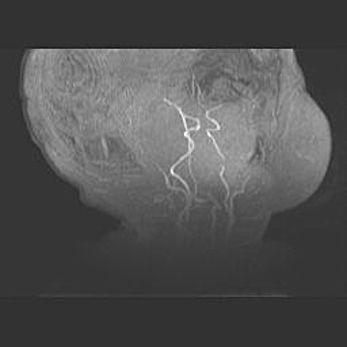

Церебральная ишемия II.

Возраст: 7 дней

Вес: 3350 г

Пол: женский

Окружность головы: 35 см

Срок гестации: 39 недель

Ишемия головного мозга – это состояние, которое развивается в ответ на кислородное голодание вследствие недостаточного мозгового кровообращения. У новорожденных она является следствием дефицита кислорода, что ведет к метаболическим расстройствам различной степени тяжести в тканях головного мозга, в том числе к развитию коагуляционных некрозов и гибели нейронов.